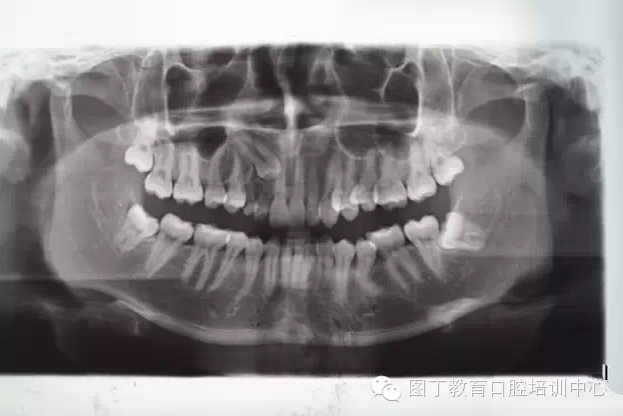

術(shù)前全景片檢查:13位于11、12根尖區(qū)。乳Ⅲ滯留。

QQ圖片20150730094928.png